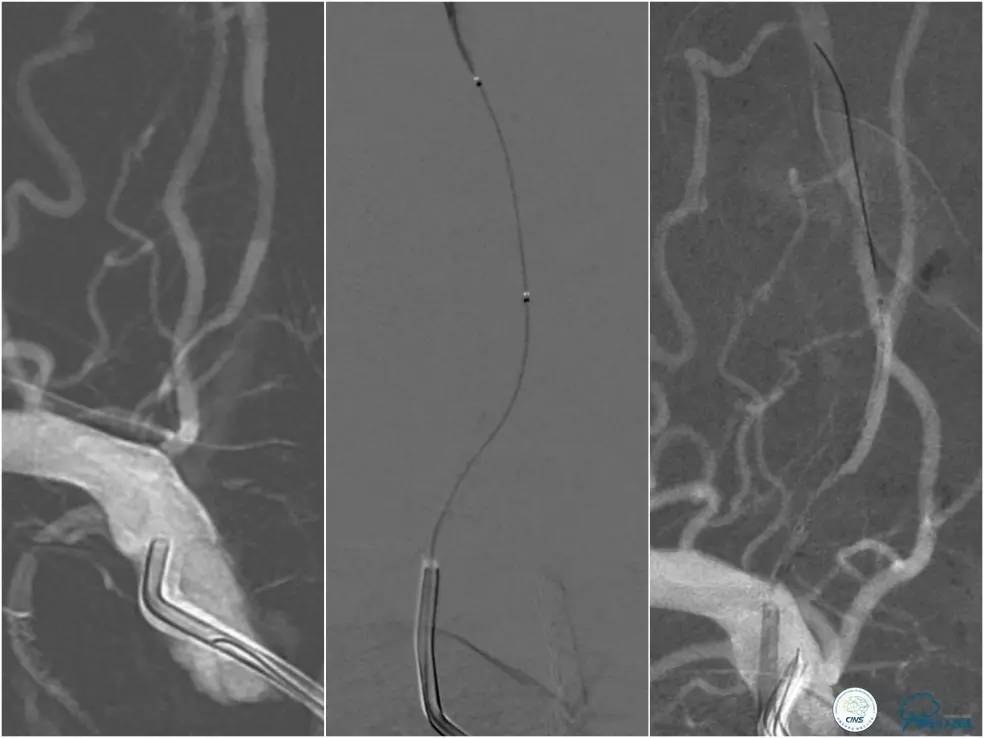

全麻下右侧股动脉穿刺置入8F动脉鞘,6F导引导管到位,送入Traxcess(0.014″200cm)微导丝+Echelon-10微导管谨慎通过右侧椎动脉V1段狭窄处至V2段远端,交换撤出Traxcess微导丝,送入Transend(0.014″300cm)微导丝至V2段远端(图10)。

图10

Ultra-Soft球囊(3.0mm×20mm)于狭窄处预扩张后置入EXCEL支架(4.0 mm× 24mm),球扩后造影见支架贴壁良好,远端血管显影好,前向血流TICI3级。6F导引导管沿微导丝通过右椎动脉V1段支架至V2段(图11)。

图11

Transend(0.014″300cm)微导丝+Echelon-10微导管,谨慎通过右椎动脉V4段病变后置于右大脑后动脉P1段(图13)。

图13

遂再次将Transend微导丝送至右大脑后动脉P1段,使用Gateway球囊(2.0mm×15mm)于支架最狭窄处后扩张(图15)。

图15